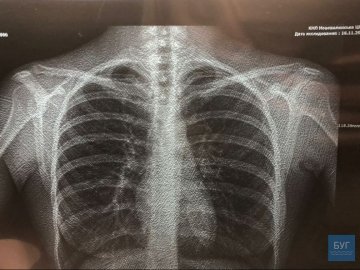

Фото на головній – знімок легень, зроблений на новому рентген-аппараті

Фото на головній – знімок легень, зроблений на новому рентген-аппараті